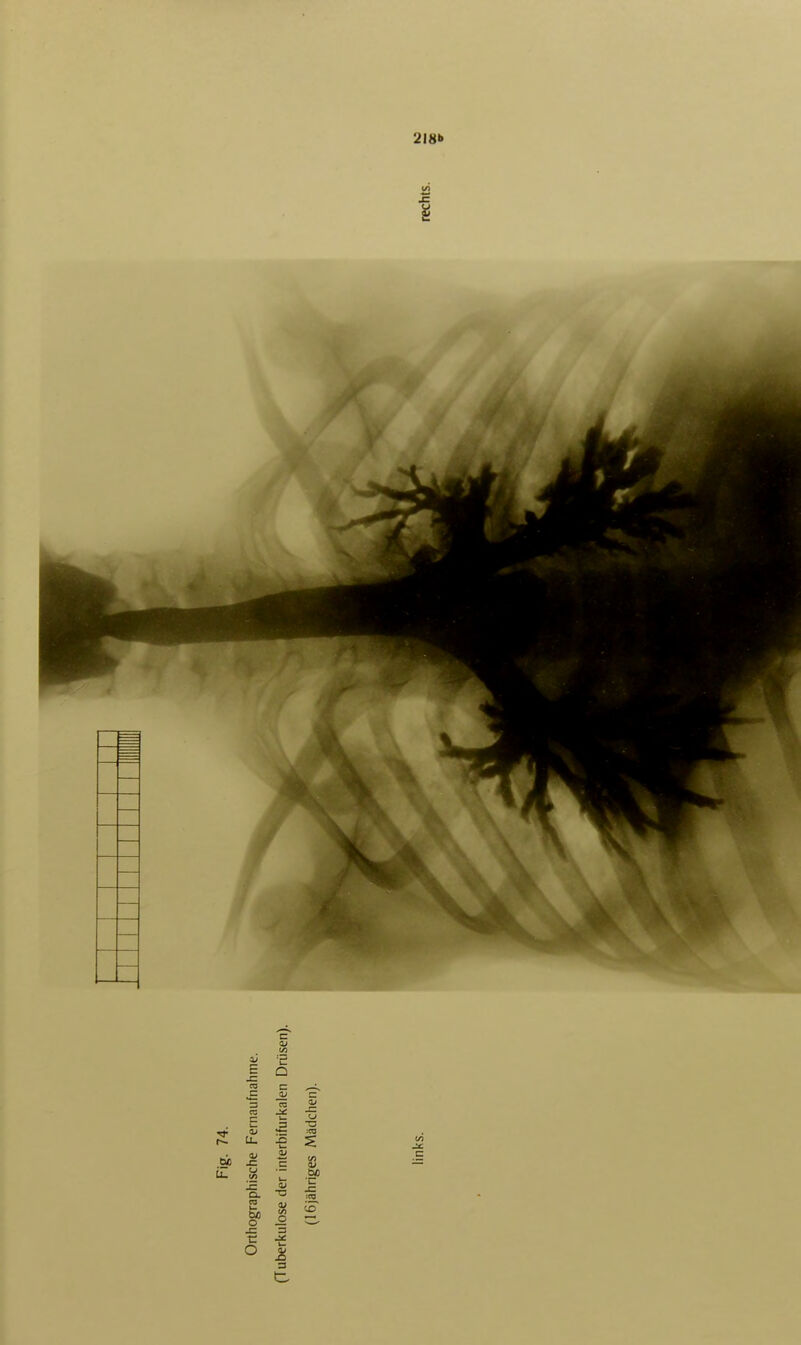

255/472 (page 218)